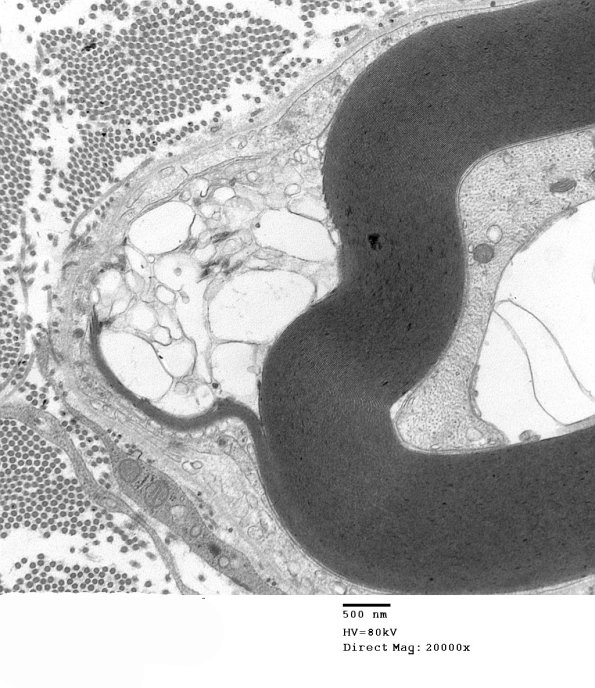

4F2 GBS, fulminant (Case 4) 137a - Copy

In this case there appears to be equivocal demyelination. (electron micrographs)